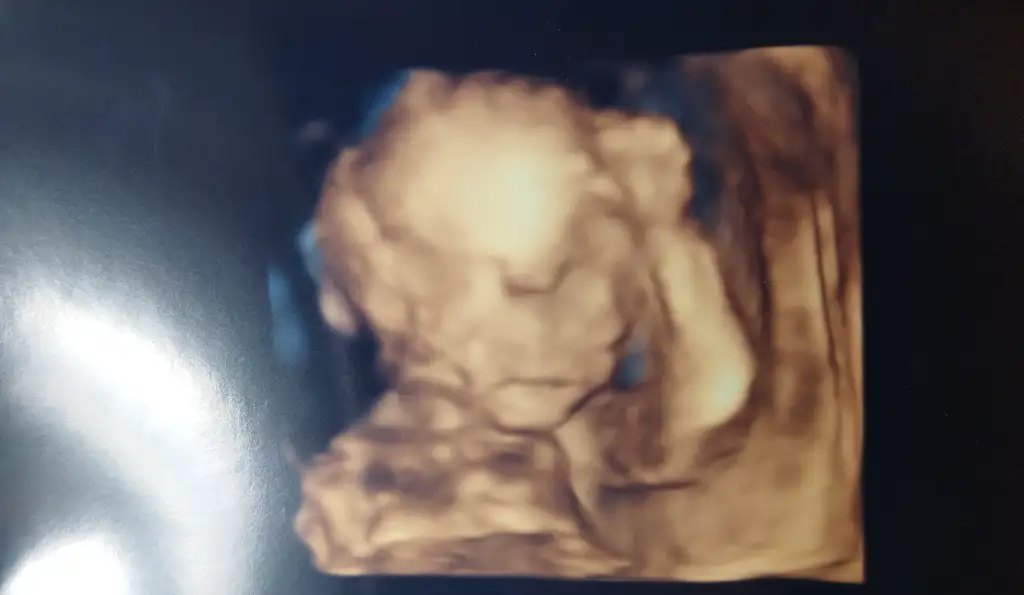

Canimm sağlıkla gelsin gözün aydın.Ne kadar da güzel görünüyorlar rabbim bizede görmeyi nasıp etsinÇıktık kontrolden teyzeleriher şey yolunda cok şükür bir sorun görünmedi hiç

Bu da kızımın son pozudaha ilk bakar bakmaz kız bebek dedi doktorumuz ilk bacak arasını gösterdi hemen sağolsun

Şimdi bir tek şeker yükleme kaldı sonrasında bir süre rahat bir nefes alırım inşallah

Maşallah darısı başımıza cok sevindim, detaylıdan ister istemez insan korkuyor insanÇıktık kontrolden teyzeleriher şey yolunda cok şükür bir sorun görünmedi hiç

Maşallah ne güzel poz vermişÇıktık kontrolden teyzeleriher şey yolunda cok şükür bir sorun görünmedi hiç